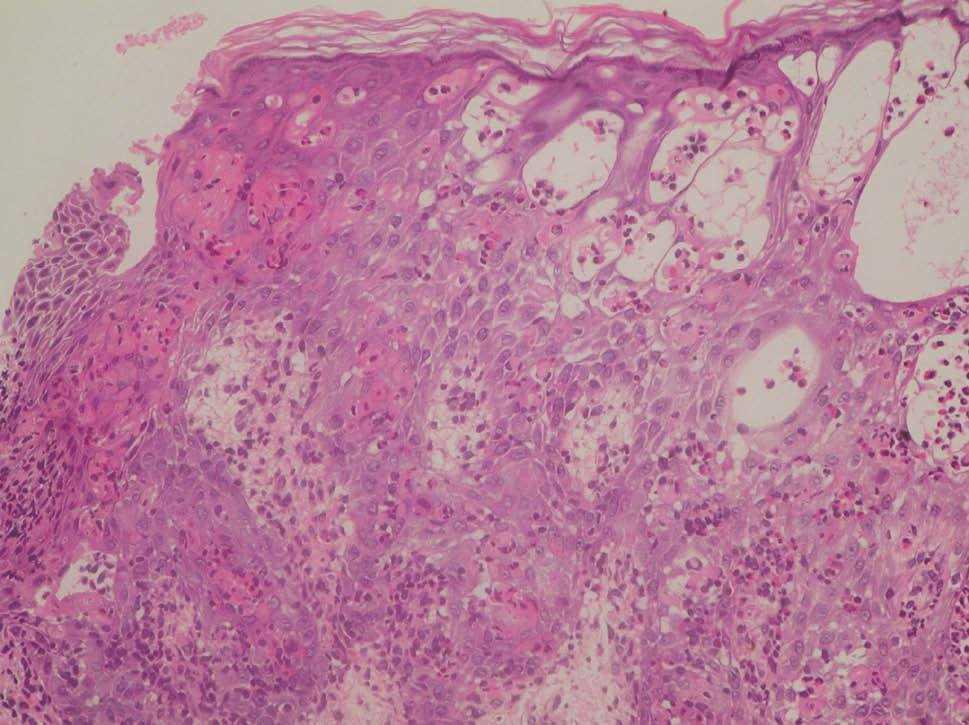

El último caso clínico corresponde a un varón, sin antecedentes familiares de interés, referido a nuestras consultas al sexto día de vida por lesiones papulovesiculosas lineales en miembro inferior izquierdo, que semanas después fueron desapareciendo, siendo sustituidas por otras lesiones hiperpigmentadas con descamación superficial más evidentes en fosa poplítea (fig. 3). Se planteó diagnóstico diferencial con otras entidades fundamentalmente NEVIL y se realizó estudio histológico, donde se evidenciaron espongiosis eosinofílica, vesículas rellenas de eosinófilos y disqueratosis focal (fig. 4), compatibles con el diagnóstico de IP. El cariotipo era normal, y tras tres años de seguimiento, permanece asintomático con involución espontánea de las lesiones cutáneas.

Figura 4. Dermatitis espongiótica eosinofílica, vesículas intraepidérmicas rellenas de eosinófilos y células disqueratósicas multiples; todos ellos son hallazgos histológicos típicos del estadio 1. (Hematoxilina-eosina, x20.)